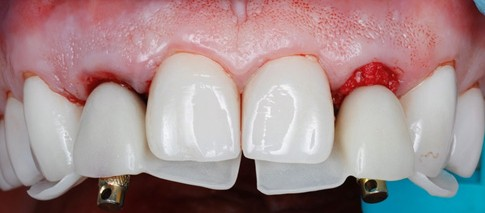

Since temp shells were already fabricated, we were ready to pick up our temporary prosthesis using non-engaging temporary abutments.

When picking up a multiple unit bridge on temporary abutments, make sure to never use flowable due to possible shrinkage of the material and only use self-curing no-shrinkage resin based material (Integrity).

Once the temporary is picked up and emergence profile is customized to have an adequate regenerative space and properly placed Critical contour (0.5 short of the final gingival margin) we are ready to deliver the prosthesis.

Prior to delivery make sure to leave a good amount of room in the embrasures to allow for soft tissue fill during the training period.